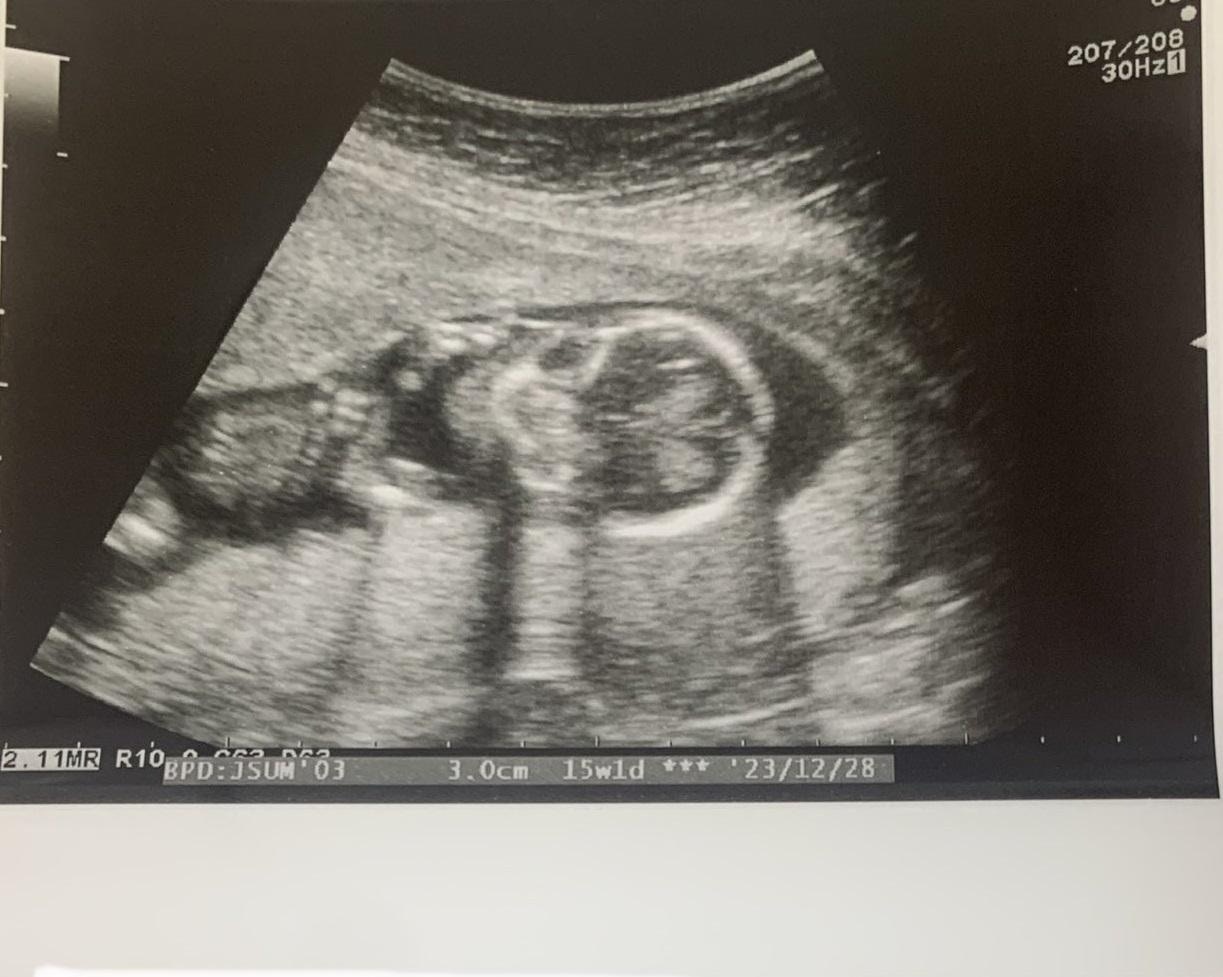

郭安妮醫師受訪時說,男性的擬娩症候群(Couvade Syndrome,又稱產翁現象),最常出現在太太懷孕初期(小於13周)與後期(大於29周),情況常會與孕婦呈現同步,例如太太睡眠不佳,丈夫也會跟著失眠;太太心情焦慮,丈夫心情隨之緊張;太太食慾起伏不定,先生也被影響,雙方體重相繼上升,而懷孕中期(13至29周)則隨著胎兒與母體情況趨於穩定,症狀變得較不明顯。

就有一名準媽媽在懷孕初期食慾不振、睡眠品質不佳,後來一度出現先兆性流產徵象,亟需安胎與多休息,丈夫雖長時間陪伴在側,但看到太太忍受孕期諸多不適,自己也開始茶飯不思,又因日夜高度緊張、焦慮而失眠,以致於產檢時面容憔悴,黑眼圈比最初得知太太懷孕時還加深不少,所幸太太在懷孕後期狀況好轉、食慾提升並增重約12到14公斤,結果丈夫為了鼓勵太太多吃也跟著進食,最後體重也在不知不覺中提高約5、6公斤。